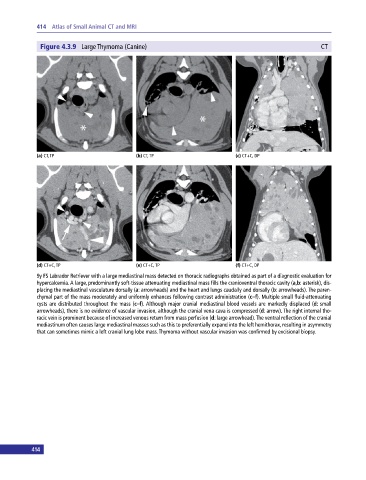

Figure 4.3.9 Large Thymoma (Canine) CT

(a) CT, TP (b) CT, TP (c) CT+C, DP

(d) CT+C, TP (e) CT+C, TP (f) CT+C, DP

9y FS Labrador Retriever with a large mediastinal mass detected on thoracic radiographs obtained as part of a diagnostic evaluation for

hypercalcemia. A large, predominantly soft‐tissue attenuating mediastinal mass fills the cranioventral thoracic cavity (a,b: asterisk), dis

placing the mediastinal vasculature dorsally (a: arrowheads) and the heart and lungs caudally and dorsally (b: arrowheads). The paren

chymal part of the mass moderately and uniformly enhances following contrast administration (c–f). Multiple small fluid‐attenuating

cysts are distributed throughout the mass (c–f). Although major cranial mediastinal blood vessels are markedly displaced (d: small

arrowheads), there is no evidence of vascular invasion, although the cranial vena cava is compressed (d: arrow). The right internal tho

racic vein is prominent because of increased venous return from mass perfusion (d: large arrowhead). The ventral reflection of the cranial

mediastinum often causes large mediastinal masses such as this to preferentially expand into the left hemithorax, resulting in asymmetry

that can sometimes mimic a left cranial lung lobe mass. Thymoma without vascular invasion was confirmed by excisional biopsy.